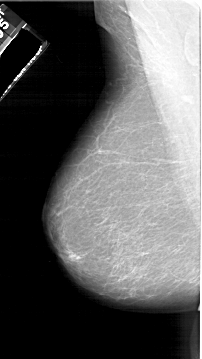

A_1161_1.RIGHT_MLO

RIGHT_MLO LINES 6181 PIXELS_PER_LINE 3781 BITS_PER_PIXEL 12 RESOLUTION 43.5 OVERLAY